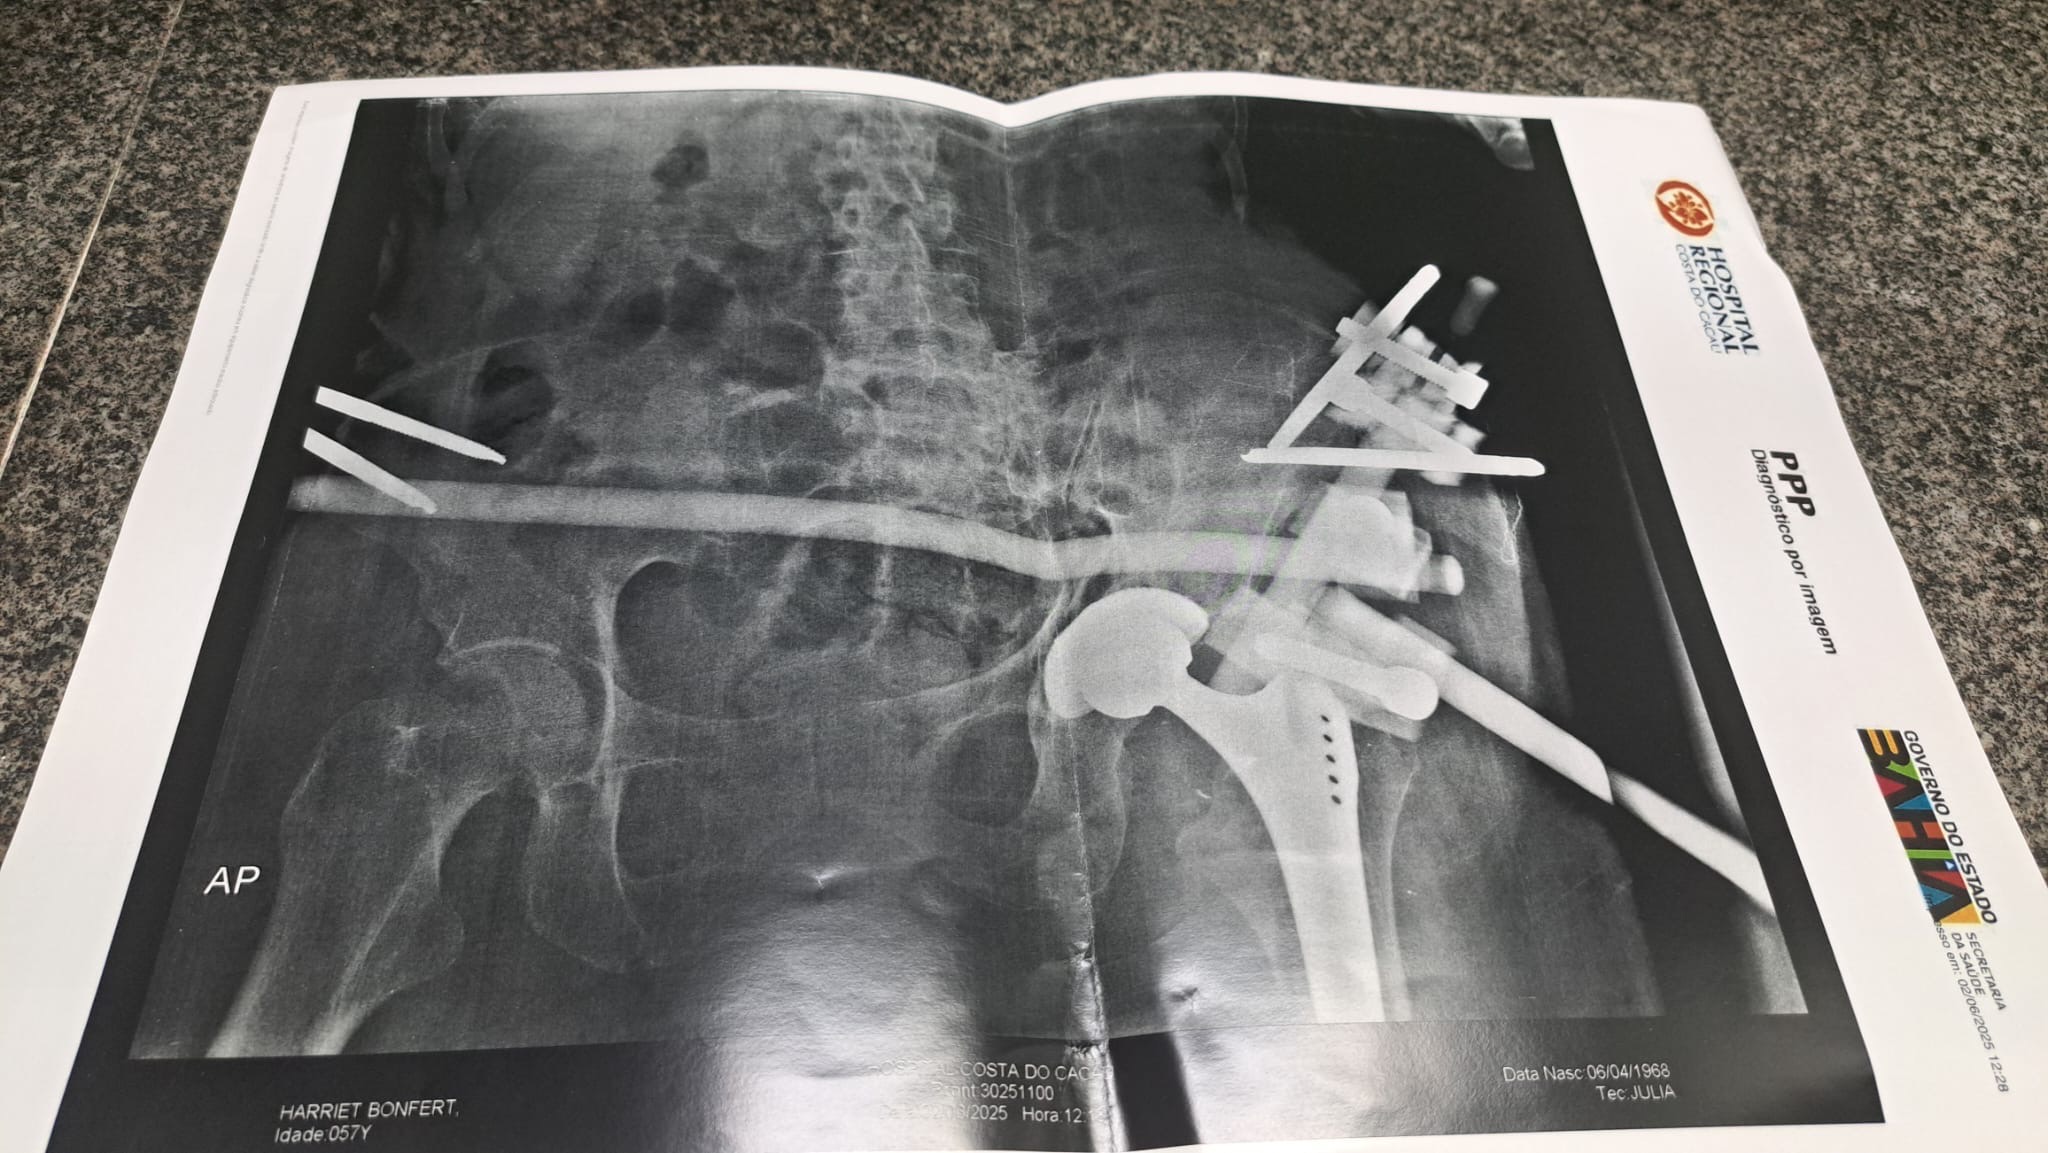

Unsere liebe Freundin Harriet wurde in Brasilien von einem Auto angefahren – ein tragischer Unfall, der ihr Leben von einem Moment auf den nächsten völlig verändert hat. Sie erlitt dabei 14 Knochenbrüche, verteilt über ihren gesamten Körper.

Seitdem liegt sie im Krankenhaus, mit unzähligen Schrauben und Metallstangen im Körper, voller Schmerzen. Die medizinischen Bedingungen vor Ort sind katastrophal, und die behandelnden Ärzte haben ihr gesagt, dass sie nichts mehr für sie tun können.